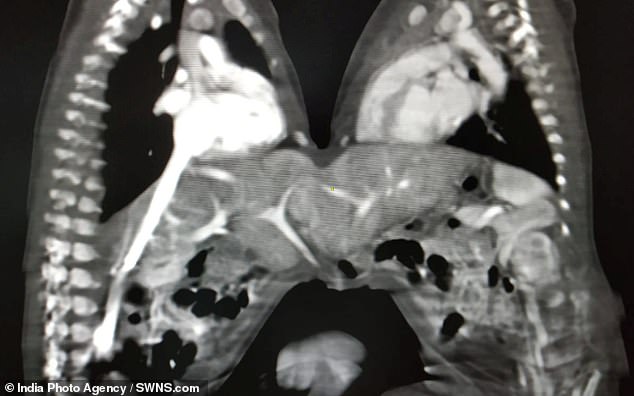

Τα κοριτσάκια – που ήταν τριών ημερών κατά τη διάρκεια της επέμβασης- ζύγιζαν μόλις 3.200 κιλά και ήταν ενωμένα στο στομάχι.

Η 5ωρη επέμβαση αποδείχθηκε επιτυχής και τα δύο κορίτσια αναμένεται να πάνε στο σπίτι τους στο τέλος αυτής της εβδομάδας.